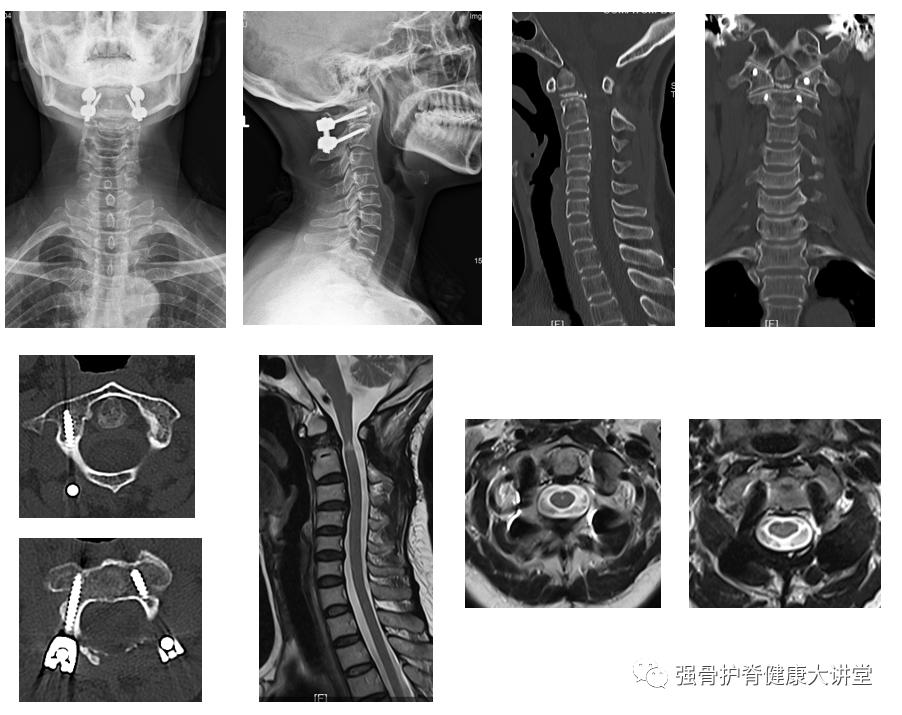

【术后复查】

颈椎X线、CT、MRI

【术后3 M复查】

颈椎X线

【术后8 M复查】

颈椎X线、CT、MRI 颈椎X线、CT、MRI

该患者为寰枢椎脱位,伴有陈旧性齿状突骨折及颈脊髓损伤。术前过伸位CT和MRI显示寰枢椎稍复位,而复位后椎管狭窄无明显改善,又枢椎骨折端存在较多骨赘,如单纯后路完全复位后恐骨赘突入椎管,加重脊髓损伤。因此,该案例需要前后路联合手术,先行前路经口撬拨枢椎骨折端进行松解同时清除骨赘,一是便于后路寰枢椎脱位复位,二是防止骨赘在复位过程中损伤后方脊髓。寰枢关节后方毗邻生命中枢延髓,进行手术治疗是恢复上颈椎正常序列、解除神经压迫、挽救患者生命的关键选择。

针对具有此类手术指征的患者,在术中轻柔、精细、高效的操作非常关键,显微镜下进行显露和操作更安全,围术期口腔护理需要由经验丰富的护理团队完成,建议这类手术需由技术成熟的团队实施,手术风险相对较大,绝大多数患者术后可快速康复,病友们有类似病情可找脊柱专科医生评估确定。